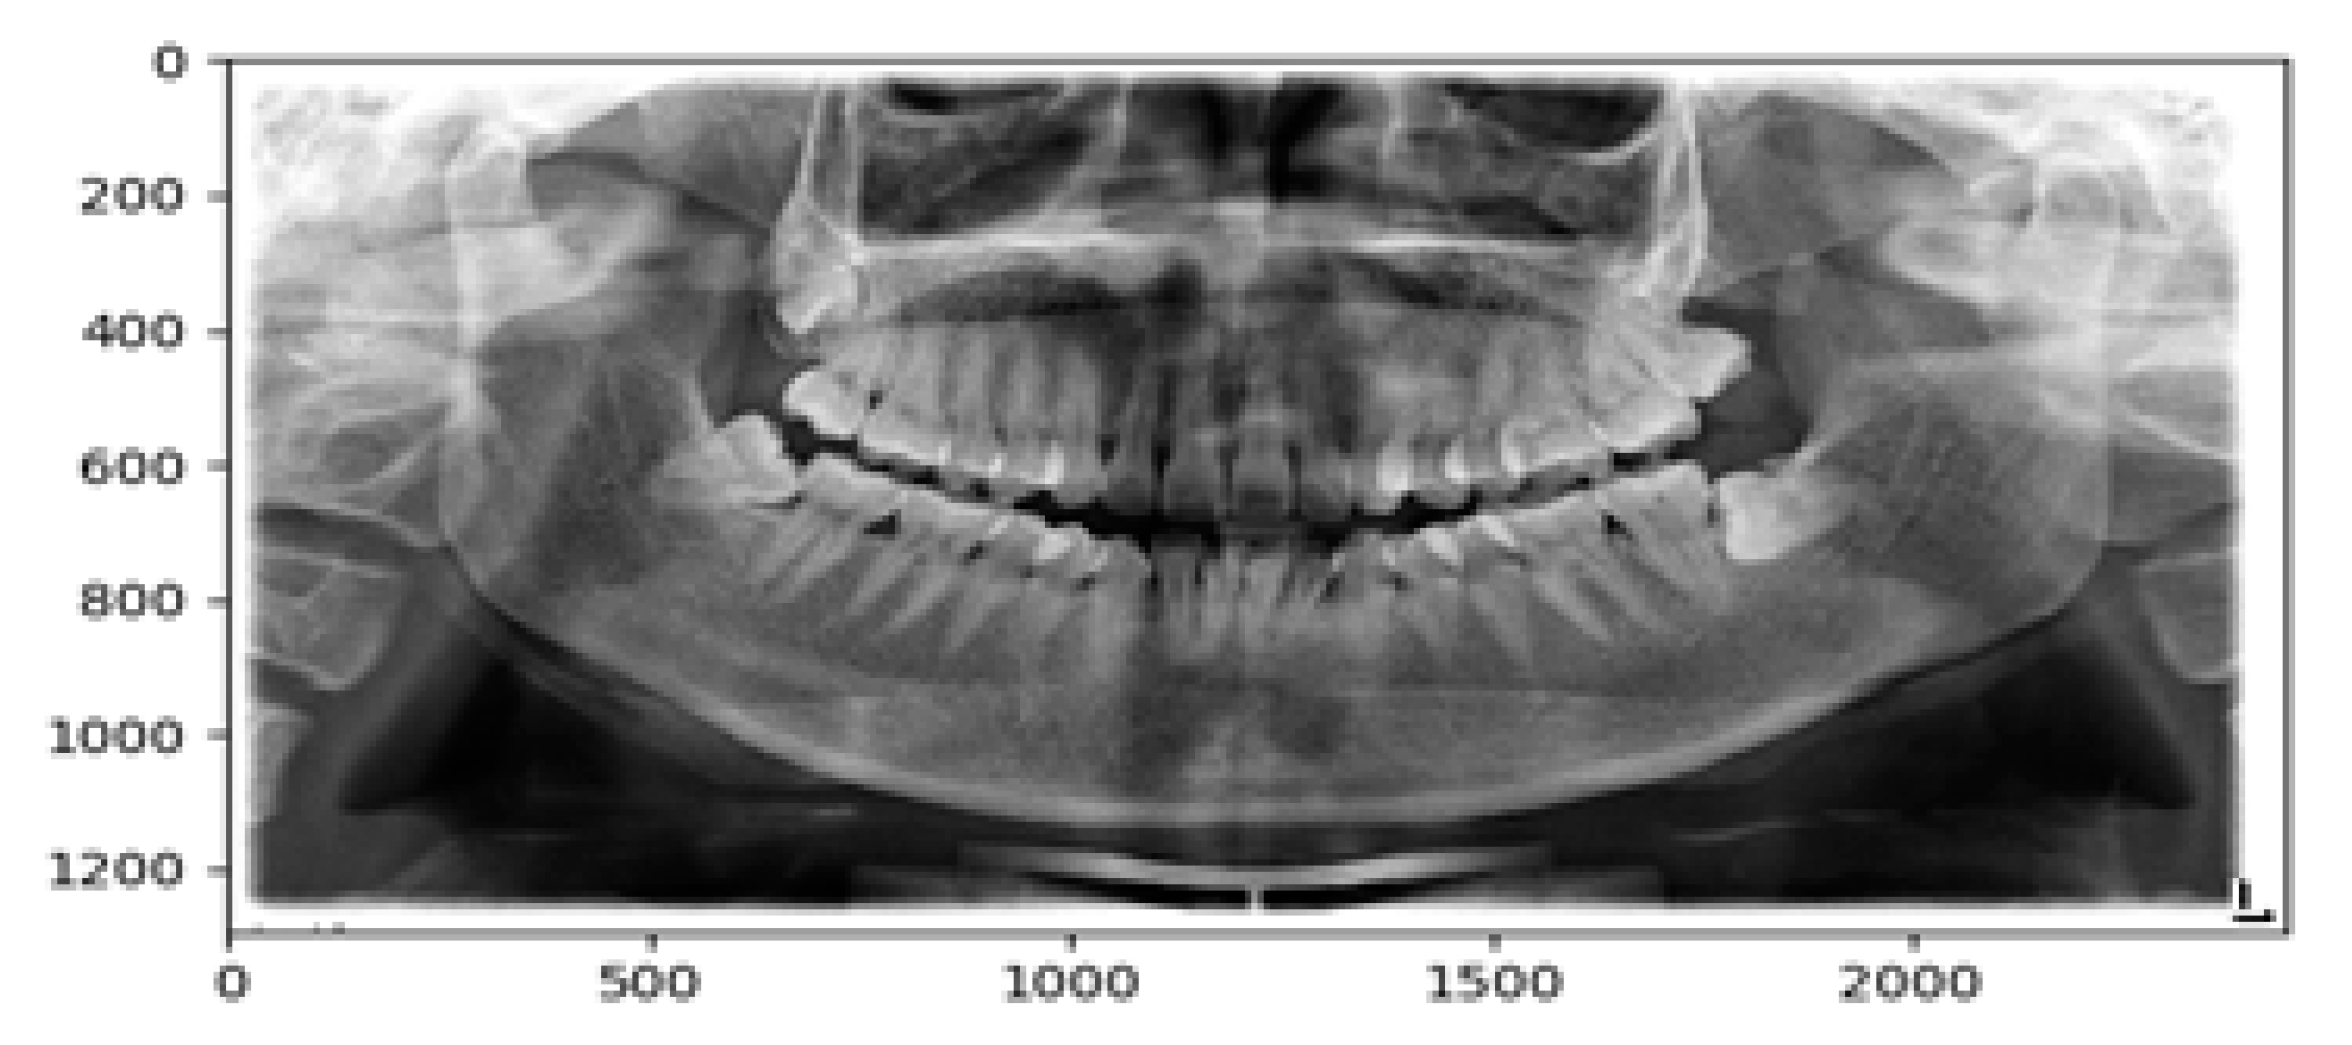

2.2.3. Image Smoothing